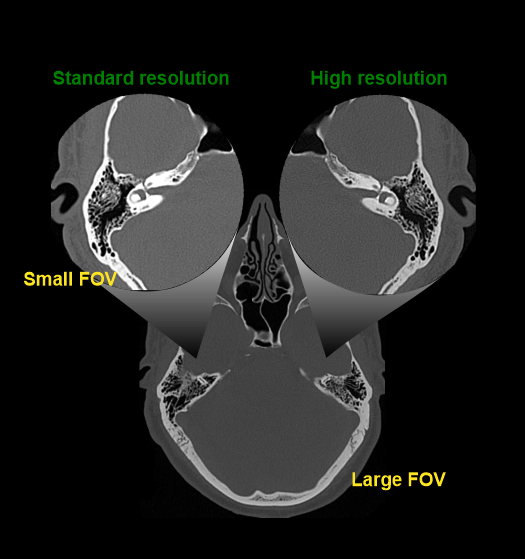

- Maximum slice thickness of 1mm in axial and coronal planes, reconstructed in bone window (WW:4500, WL:450) to show both canals in the same plane.

Explanation: Small-FOV reconstruction and high-resolution algorithms can be used to improve the image quality.